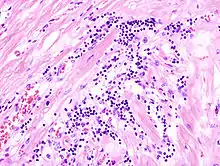

Virale Myokarditis

Ät.: Coxsackie-, ECHO-, Adenoviren, Influenzaviren

Pathogenese: Herzmuskelnekrose durch Virus und T-Zell-vermittelte Immunreaktion.

Mikro: Interstitielles lymphozytäres Infiltrat (kleine blaue Zellen), kaum Nekrosen.

![]() Virale Myokarditis bei Patient mit plötzlichem kongestiven Herzversagen, Autopsiepräparat, H&E. |